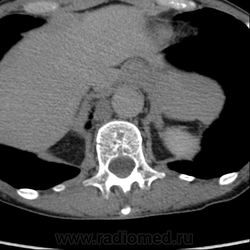

Обнаружилось небольшое образование низкой плотности, с достаточно ровными, четкими контурами парааортально справа около ножки диафрагмы на уровне тела L1 позвонка.

При нативе плотность 6HU, паренхиматозная - 18-20HU, экскреторная (15 минут) - 60-65HU.

Выкладываю по очереди срезы на одинаковых уровнях, сначала паренхиматозная, потом отсроченная фазы.